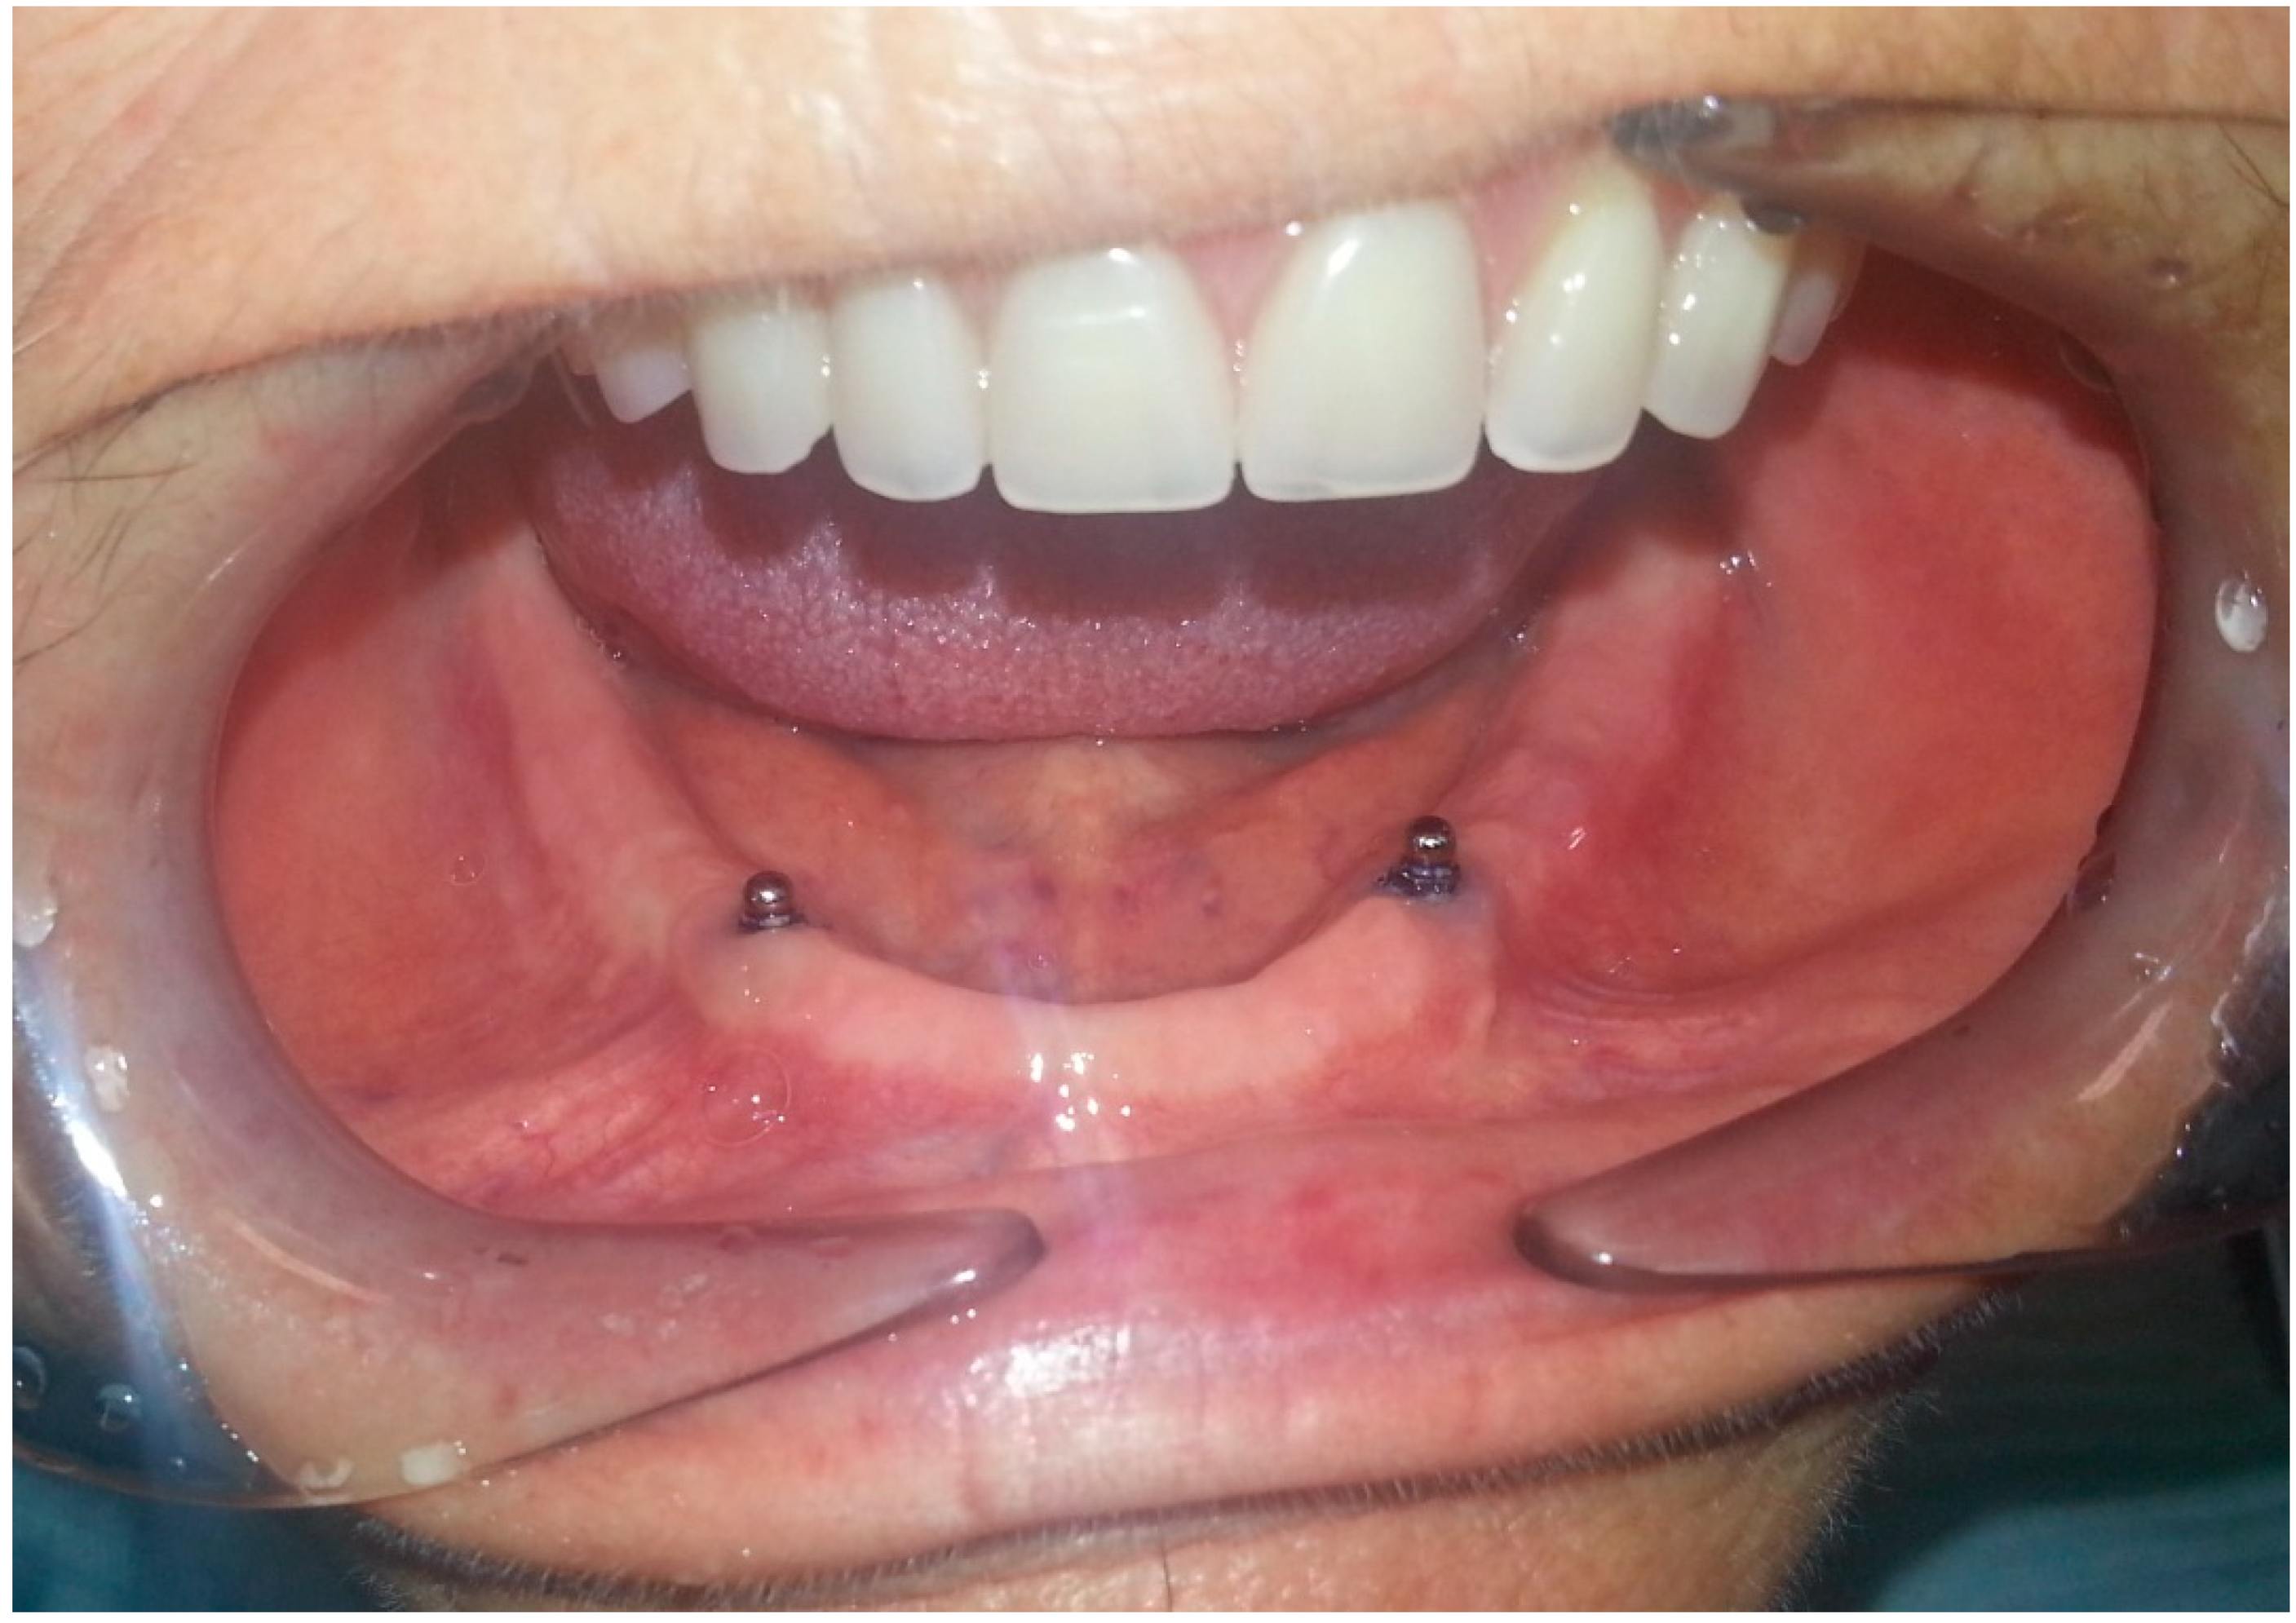

- After 7 days, the Teflon/o-ring is replaced. After preparing the housing for the Teflon on the mobile prosthesis and evaluating the necessary height, insert the small silicone tube cut at the right height in the ball-attachment. Then, the Teflon is inserted. The silicone tube adheres superiorly to the Teflon inferiorly to the gingiva protecting the entire retentive attachment (Figure 4, Figure 5, Figure 6 and Figure 7). After mixing the acrylic resin and inserting it in the right quantity (filling the previously prepared cavity 50%), the prosthesis is fitted into the oral cavity, causing the patient to close in full intercuspidation and waiting for polymerization (Figure 8, Figure 9 and Figure 10). Once the polymerization has taken place, the mobile prosthesis can be removed very easily as the acrylic resin will be present only around the Teflon and will have filled all the walls of the cavity previously prepared leaving them smooth; there may be small smears of resin that will easily be removed in a short time with the aid of rubber pads (Figure 11).